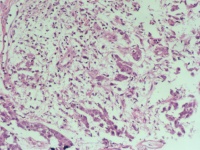

性别

男

年龄

56岁

临床诊断

肺占位

一般病史

CT发现右下肺占位性病变

标本名称

纤支镜活检

大体所见

合约1*0.8*0.3cm灰红组织多枚

鳞癌

主要是鳞,不过图5图6那样的区域有没有腺不好说,最好标一下。